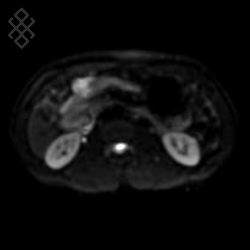

IRM Pancréatique

La durée moyenne de l'examen est de 25 min. Dans le cas d'une injection, le manipulateur en radiologie vous administrera le produit de contraste. Vous entendrez un bruit caractéristique à l'IRM faisant penser à un marteau piqueur.